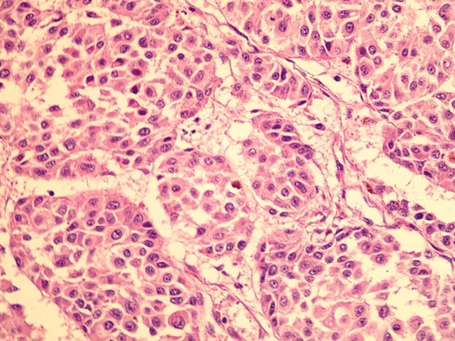

Morfología característica del melanoma, imagen con aumento medio de un melanoma nodular. Foto: Dr. Ahmet Cemil Kaur. Autores del artículo: Zekayi Kutlubay, Burhan Engin, Server Serdaroğlu and Yalçın Tüzün/CC BY 3.0, via Wikimedia Commons.

En la Universidad de Tel Aviv, un grupo de científicos realizó un estudio sobre modelos animales con melanoma. A partir de esa investigación, descubrieron una nueva tecnología que produce la eliminación de las células cancerígenas a partir de una toxina que se produce a partir de una bacteria.